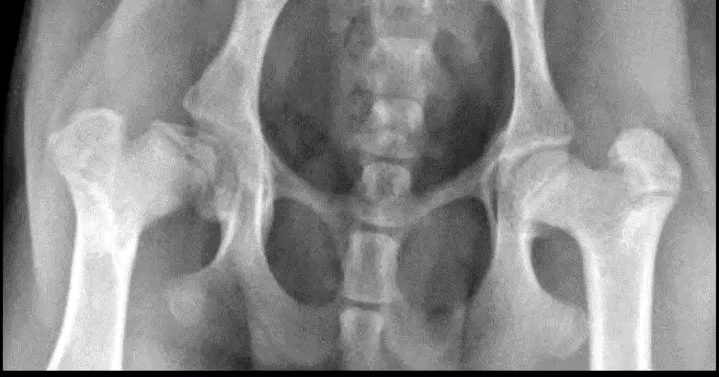

What are the radiographic changes of avascular necrosis of the femoral head?

Widened joint space from thickened cartilage

Increased opacity in the epiphyseal area of femoral head

Focal bony lysis femoral head

Muscle atrophy and secondary DJD

What is the earlies radiographic change from avascular necrosis of the femoral head?

Avascular necrosis of the femoral head